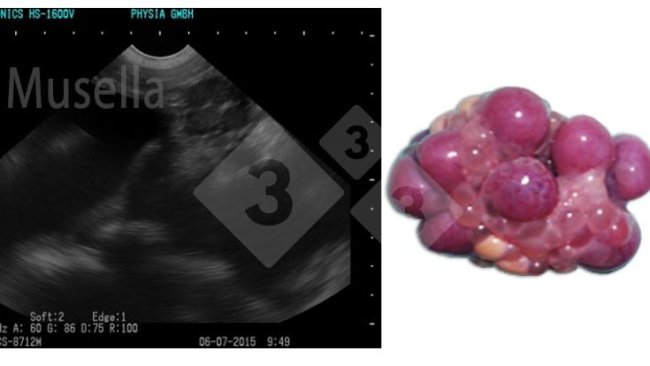

利用高清晰度超声波设备的新技术,能够识别母猪周期的阶段(可在排卵前或排卵后不久进行授精),在科学上是非常有价值的方法,但是,由于对从事该项工作的人有一个很高的要求,因需对卵泡生长进行监测,以及对发情周期的时间的监测,需要每天进行几次观察,因此在猪场中难以实施。